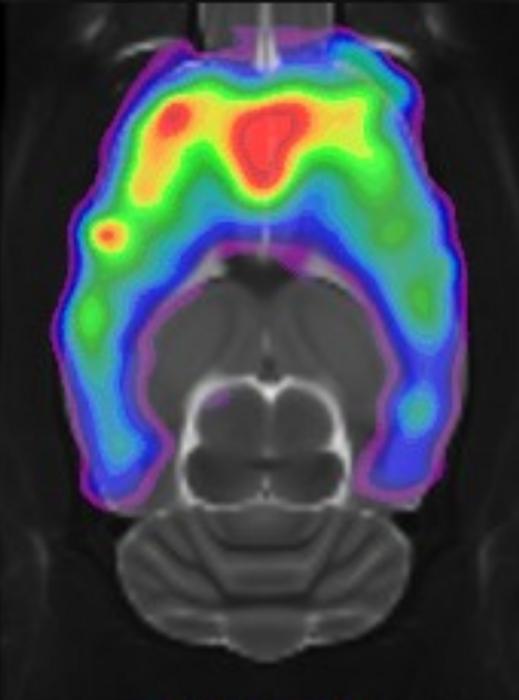

Scan of a rat brain showing the serotonin 5-HT2A receptor affected by psylocobin.

Mikael Palner, University of Southern Denmark